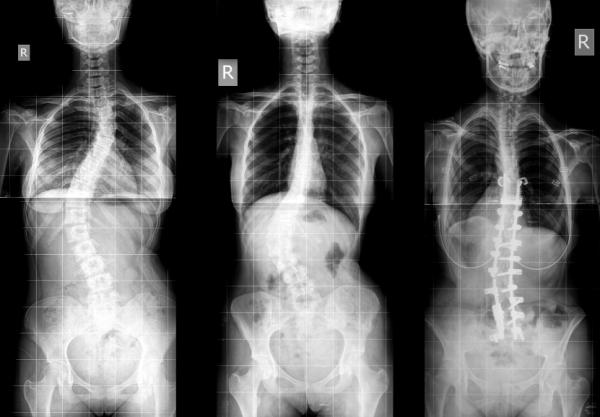

La escoliosis es la curvatura anormal de la columna vertebral, generalmente en forma de S o C. Nuestra columna tiende a curvarse de manera natural, pero para las personas con esta condición, la curva resulta exagerada. La escoliosis idiopática suele ser la más común y es la que no tiene una causa específica, es más común en niñas y en la etapa donde el crecimiento es más acelerado. En ONsalus te explicamos los tipos, síntomas y tratamiento de la escoliosis

Existen tres tipos de escoliosis y se subdividen con relación a la edad del paciente y en la parte del cuerpo donde comenzó el desarrollo. La más común es la escoliosis idiopática, se divide en infantil, si está presente en niños de 3 o menos años, juvenil si es entre los 4 y 10 años y adolescente entre los 12 y 18 años. El segundo tipo de escoliosis es la congénita, se presenta al nacer y ocurre cuando no hay una formación correcta de las costillas o vértebras del bebé. Por último tenemos la escoliosis neuromuscular,que generalmente, es más bien un síntoma secundario de enfermedades que producen alteraciones en el sistema nervioso como espina bífida, distrofia muscular, polio o parálisis cerebral.

La escoliosis no tiene síntomas y tampoco produce dolor. Aunque es notoria la asimetría en los hombros, curvatura en la columna que se inclina hacia un lado, omóplatos prominentes y caderas desniveladas. Para diagnosticar la escoliosis, el médico realizará un examen físico que consistirá en agacharse hacia adelante para notar la asimetría, también se tomarán radiografías para ver qué tan grave es la curvatura.

La cirugía es otro de los tratamientos para la escoliosis, la idea es corregir la curva, y las vértebras se sostendrán con varillas de metal, la técnica quirúrgica es compleja y no está exenta de riesgos. Luego de la intervención es posible que deba seguir usando el corsé por un tiempo